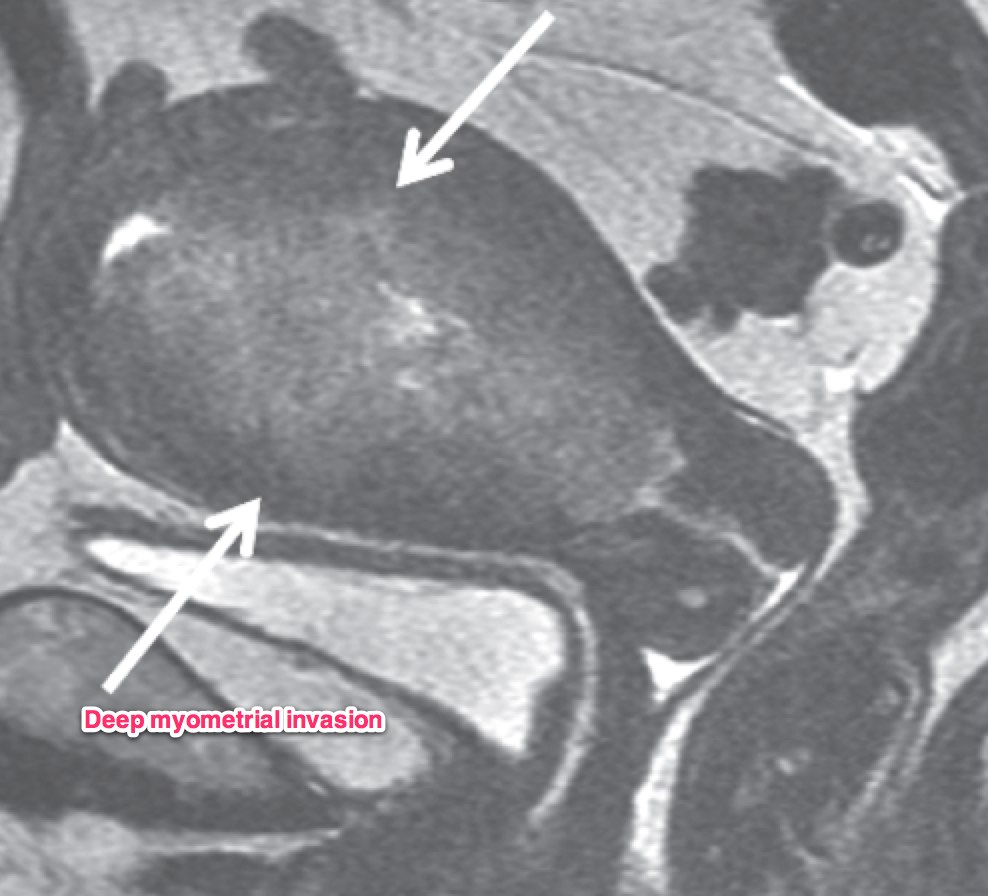

A transvaginal ultrasound should be obtained. In post-menopausal women, the expected endometrial thickness is < 4 mm. In pre-menopausal women, the thickness varies with the menstrual cycle. MRI is useful in identifying suspicious hyperplasia. If a thickened myometrium is visible on contrast enhanced CT, it is likely there is > 50% myometrial invasion. Cervical stromal invasion is seen on CT as an enlarged cervix, > 3 cm, heterogeneous stroma with low attenuation. Parametrial invasion is seen by loss of fat in the periureteral region, and fat plane near the pelvic sidewall.

Dynamic contrast enhanced MRI is optimal for MRI studies with accuracy of 85% or better. If there is a clear junctional zone between the tumor and the myometrium, the disease is most likely limited to the myometrium. MRI can also determine depth of cervical stromal invasion.

GOG 99 (Keys) found a local recurrence rate of 12% (observation) v. 3% (whole pelvic RT), but no survival benefit at 86% (obs) v. 92% (WPRT, p=0.56). A subgroup analysis restricted to High intermediate risk groups and stratified by age was performed. Three risk factors were examined: LVSI, Grade 2-3 and deep myometrial invasion. They found a 2 year recurrence rate of 26% in the observation arm and 6% in the radiation arm.

Tumor grade is a good prognostic indicator. Grade is directly related to the depth of myometrial invasion and nodal metastases.